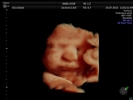

Fotografías de ecografías 4D HD/5D

Haga click sobre las imágenes para ampliar